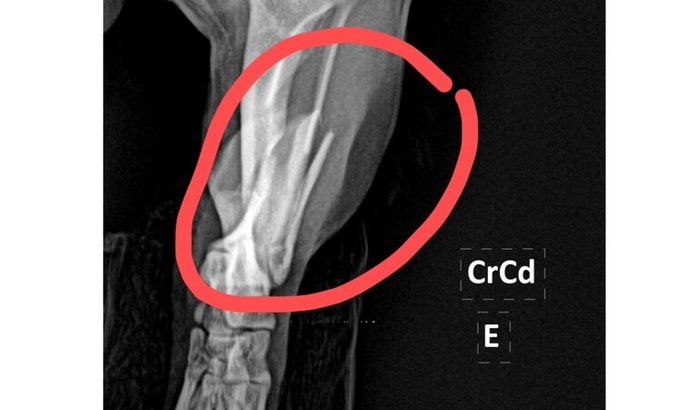

O Fredy Bento é um mini Shih-tzu de apenas 2 anos, pequeno no tamanho, mas gigante no amor que traz pra nossa casa. Ele é nosso companheiro de todos os dias, nosso conforto nos momentos difíceis e a alegria que corre pela casa.Infelizmente, o Fredy sofreu um acidente inesperado e acabou fraturando a tíbia e a fíbula da perninha traseira esquerda. Desde então, nosso coração está apertado ao vê-lo com dor, sem conseguir apoiar a patinha e sem entender o que aconteceu.Os veterinários foram claros: ele precisa de cirurgia ortopédica com urgência para não ficar com sequelas e poder voltar a andar, correr e brincar como antes. O custo da cirurgia, exames, medicações e recuperação é alto e, no momento, está além das nossas condições.Criamos essa vakinha com muita humildade e esperança. Qualquer valor ajuda — e se você não puder contribuir financeiramente, compartilhar já é um gesto enorme de amor.Estamos lutando para dar ao Fredy a chance de uma recuperação digna, sem dor e com muito carinho.Agradecemos de coração a todos que puderem nos ajudar 🤍🐶

Viemos aqui trazer uma boa notícia e agradecer de coração.O Fredy já passou pela cirurgia ortopédica, e graças a Deus o procedimento foi um sucesso 🙏🐶Ele está em recuperação, sendo acompanhado de perto, tomando os remédios e se adaptando aos cuidados do pós-operatório. Ainda é um processo delicado, mas ele vem reagindo muito melhor do que imaginávamos, o que enche nosso coração de esperança.Os custos, infelizmente, foram além da cirurgia em si. Entre exames, medicações, adaptações em casa e cuidados contínuos, os gastos aumentaram bastante e ainda teremos despesas ao longo da recuperação.Seguimos com a vakinha ativa porque toda ajuda continua sendo essencial nesse momento.Cada contribuição, cada compartilhamento e cada mensagem de carinho têm feito toda a diferença.Obrigada, de verdade, a todos que estão ajudando o Fredy a se recuperar 🤍🐾